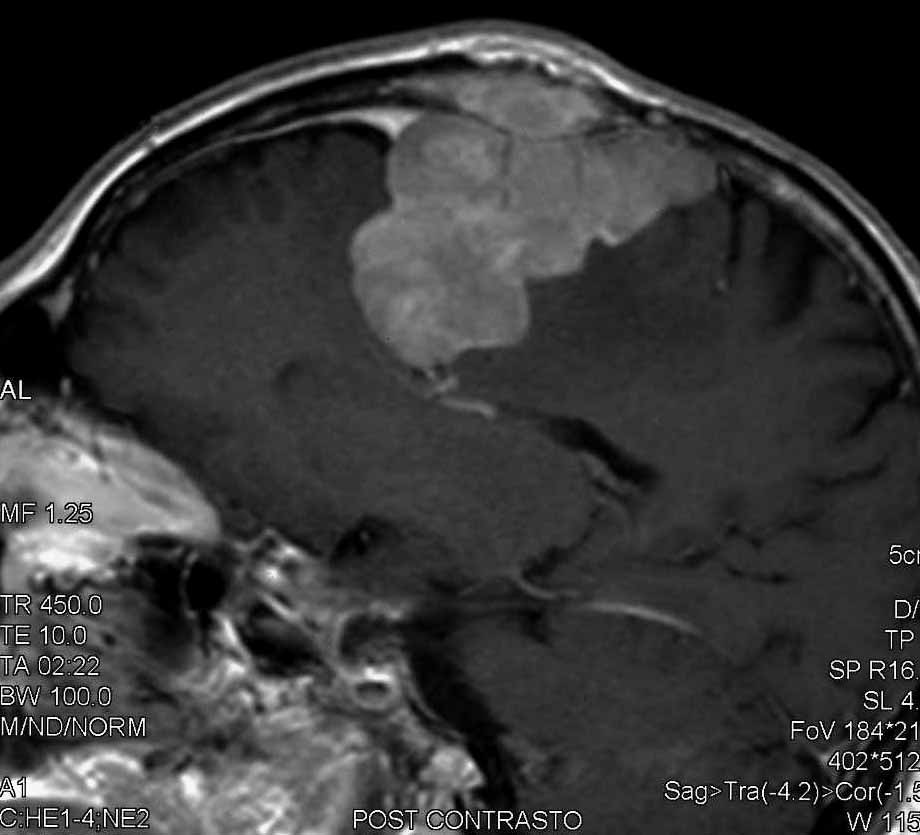

Meningioma |

| Meningioma

con demolizione-ricostruzione della teca cranica in un unico tempo

con tecnica microchirurgica e neuronavigazione. |